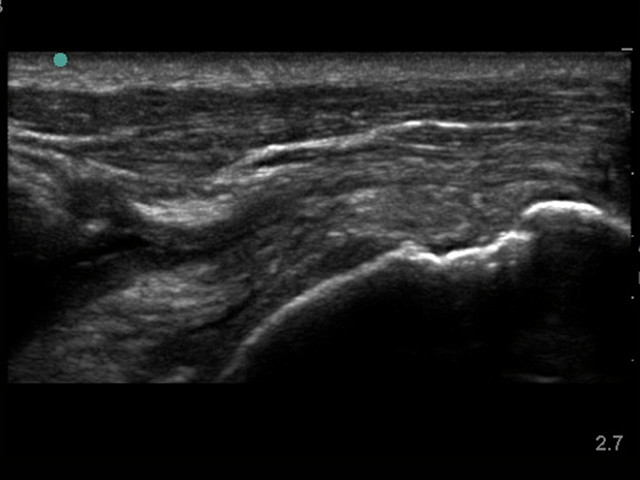

Shoulder Supraspinatus Post Operative Intact Image